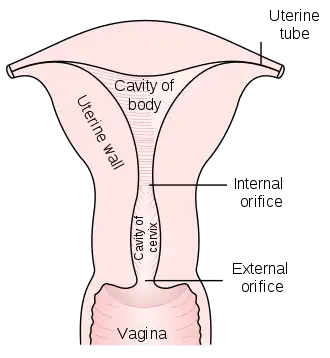

The cervical canal is the spindle-shaped, flattened canal of the cervix which connects the vagina to the main cavity of the uterus in most mammals.

The cervical canal communicates with the uterine cavity via the internal orifice of the uterus (or internal os) and with the vagina via the external orifice of the uterus (ostium of uterus or external os). The internal orifice of the uterus is an interior narrowing of the uterine cavity. It corresponds to a slight constriction known as the isthmus that can be seen on the surface of the uterus about midway between the apex and base. The external orifice of the uterus is a small, depressed, somewhat circular opening on the rounded extremity of the cervix, opening to the vagina. Through this aperture, the cervical cavity communicates with that of the vagina.

The external orifice is bounded by two lips, an anterior and a posterior. The anterior is shorter and thicker, though it projects lower than the posterior because of the slope of the cervix. Normally, both lips are in contact with the posterior vaginal wall. Prior to pregnancy, the external orifice has a rounded shape when viewed through the vaginal canal (as through a speculum). Following childbirth, the orifice takes on an appearance more like a transverse slit or is "H-shaped".